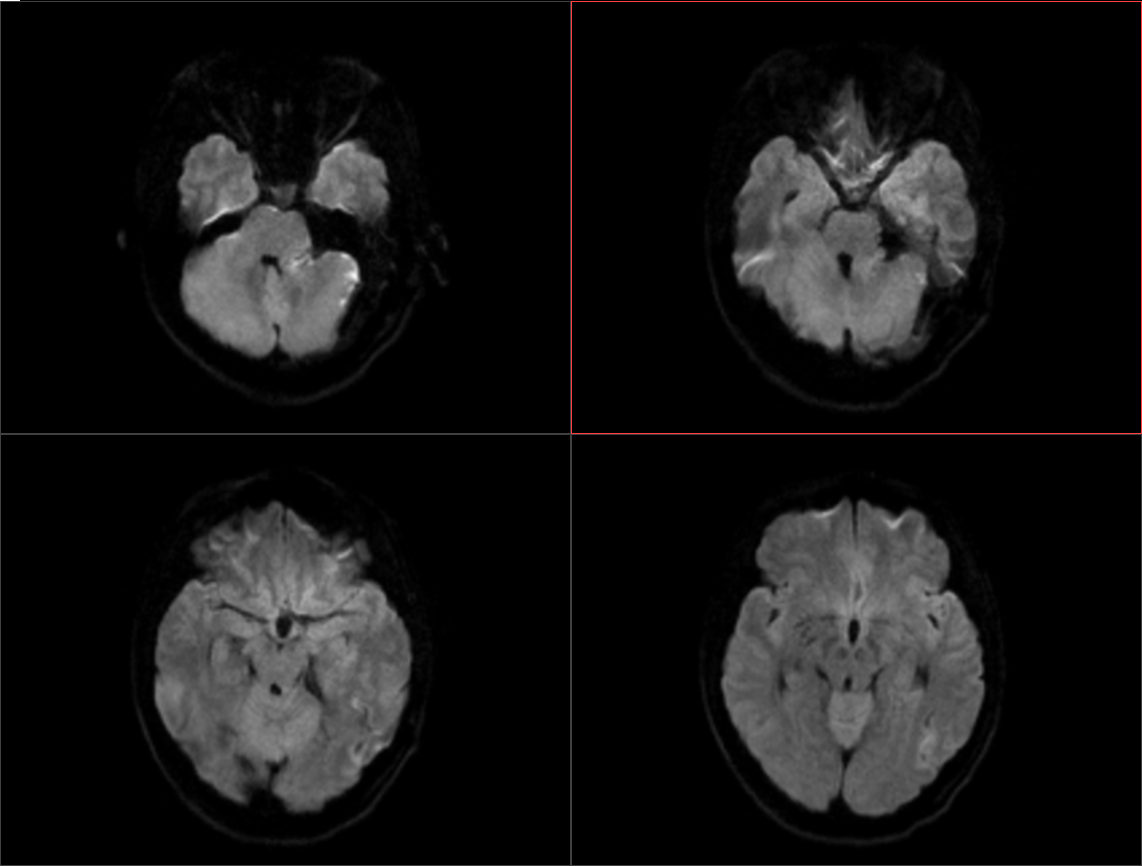

术后影像: